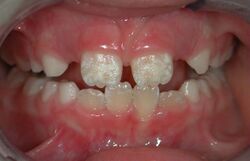

The majority of dental treatments are carried out to prevent or treat the two most common oral diseases which are dental caries (tooth decay) and periodontal disease (gum disease or pyorrhea). Common treatments involve the restoration of teeth, extraction or surgical removal of teeth, scaling and root planing, endodontic root canal treatment, and cosmetic dentistry[9]